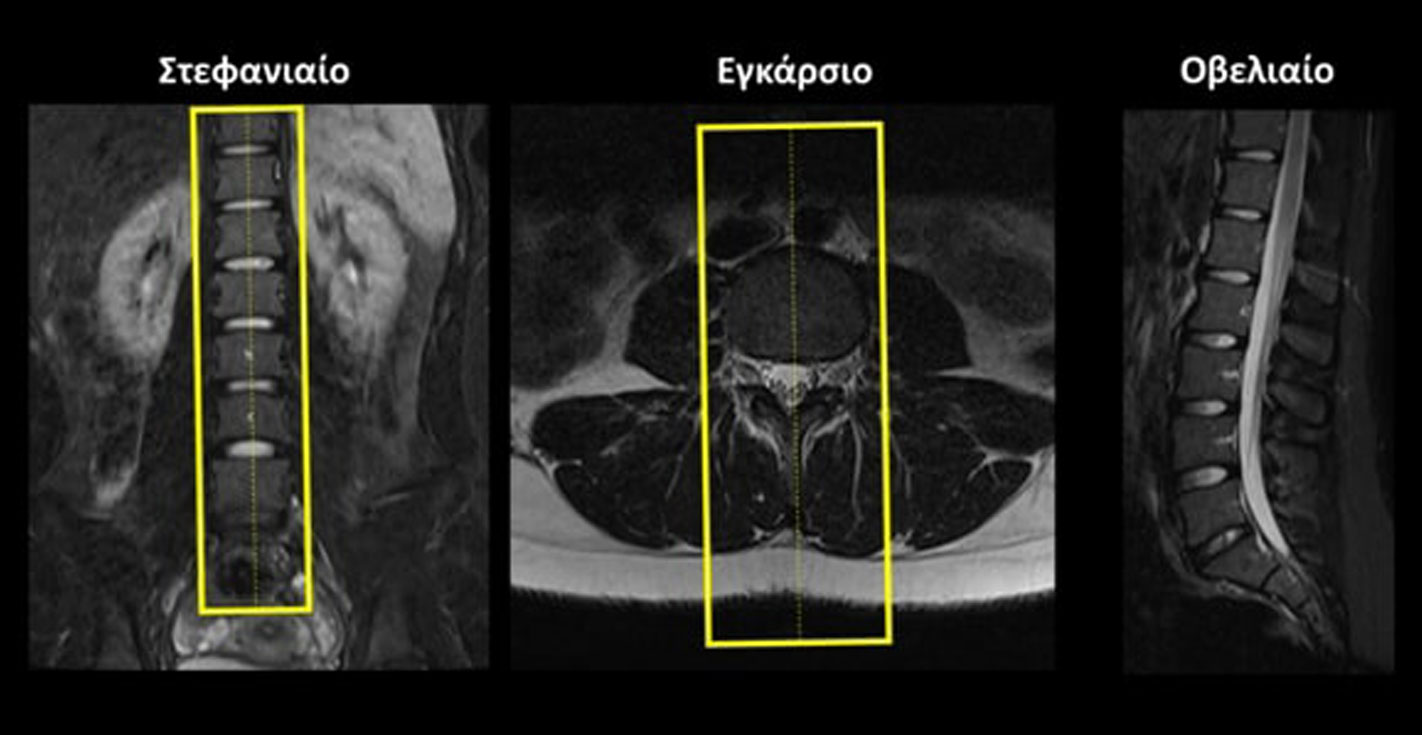

Σχεδιασμός τομών

Οβελιαίο (Sagittal): οι οβελιαίες τομές σχεδιάζονται παράλληλα με τους 5 οσφυϊκούς σπονδύλους στο στεφανιαίο επίπεδο και παράλληλα με την νοητή γραμμή που ενώνει το σπονδυλικό σώμα και την ακανθώδη απόφυση στο εγκάρσιο επίπεδο. Οι τομές πρέπει να περιλαμβάνουν ολόκληρα τα σπονδυλικά σώματα από τα δεξιά έως τα αριστερά.

Στεφανιαίο (Coronal): οι στεφανιαίες τομές σχεδιάζονται παράλληλα με το σπονδυλικό κανάλι στο οβελιαίο επίπεδο και κάθετα στην νοητή γραμμή που ενώνει το σπονδυλικό σώμα και την ακανθώδη απόφυση στο εγκάρσιο επίπεδο. Οι τομές πρέπει να περιλαμβάνουν ολόκληρα τα σπονδυλικά σώματα και το σπονδυλικό κανάλι από μπροστά μέχρι πίσω.

Εγκάρσιο (Axial/Transversal): οι εγκάρσιες τομές συνήθως λαμβάνονται ως 5 ξεχωριστά πακέτα και σχεδιάζονται παράλληλα με τον κάθε έναν μεσοσπονδύλιο δίσκο, τόσο στο οβελιαίο όσο και στο στεφανιαίο επίπεδο. Οι τομές πρέπει να περιλαμβάνουν ολόκληρους τους μεσοσπονδυλίους δίσκους από πάνω έως κάτω.